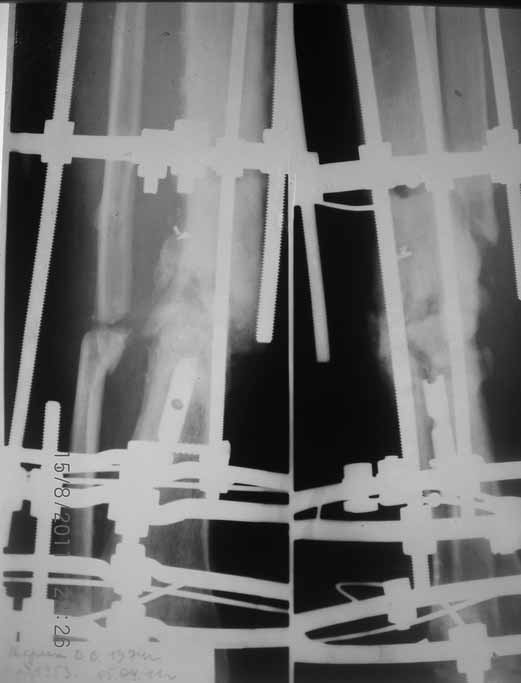

Уважаемые коллеги благодарю Вас за проявленный интерес к данной проблеме! Пересылаю Вам внешний вид правой голени.

Как-то вот нет уже желания открываться в зоне ложного сустава. Мы бы

попытались сделать закрыто. Винт в дистальном отломке удалить через прокол.

Кусок гвоздя оставить. Новый гвоздь (солидный), возможно с покрытием.

Примерная ситуация. Пациент 37 лет. Синтезировали где-то пластинкой. Попал к нам через 2 месяца.

19 апреля убрали через проколы пластину с винтами, пересекли fibula, наложили аппарат.

Немного потянули по оси, убрали вальгус, ротацию. 22 апреля (на 3-е сутки) заштифтовали окончательно. 29 апреля выписали из отделения. На все ушло 10 дней.